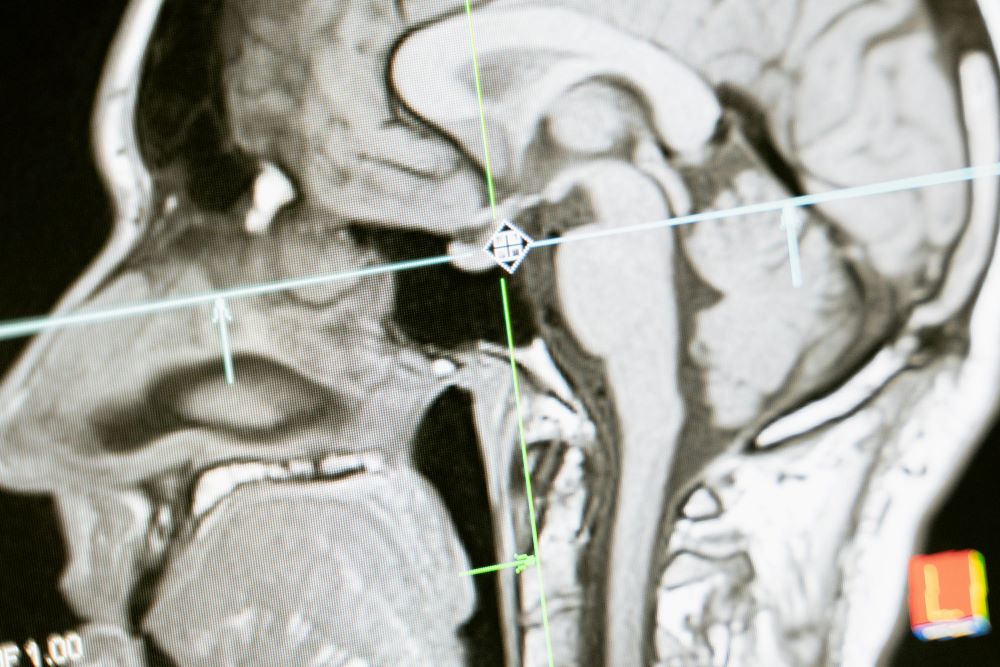

Recent advancements in artificial intelligence are transforming the field of medical imaging, particularly in detecting and analyzing tumors through PET and CT scans, which have long been used for diagnosing cancer by identifying the size, location, and characteristics of tumors. PET scans reveal how tissues use energy, often with a radioactive form of glucose to highlight areas of abnormal activity indicating the presence of malignant tumors. CT scans, on the other hand, use X-rays to create detailed cross-sectional images of the body, helping pinpoint the exact location of these issues.

For cancer patients, imaging is often necessary to track multiple lesions caused by tumor growth. This manual process requires physicians to go through hundreds of images to identify and measure abnormalities, which is not only labor-intensive but also time-consuming. The introduction of AI-based algorithms is changing this landscape, offering ways to automate the evaluation process while maintaining or even enhancing accuracy.